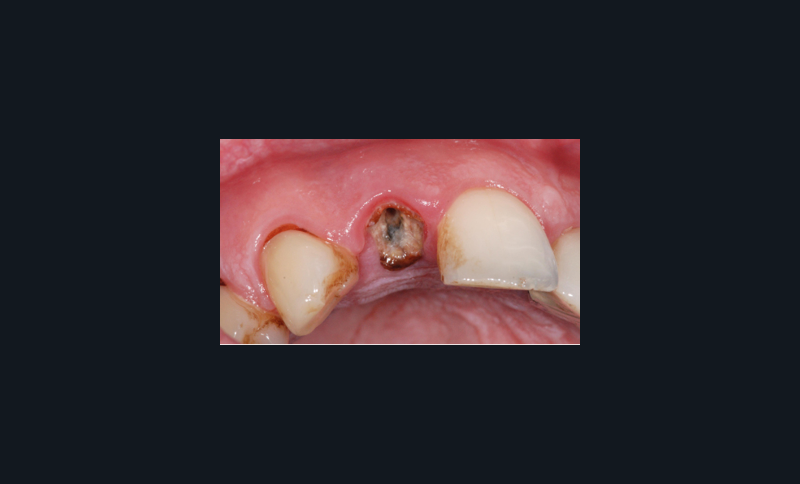

Nous allons décrire, étape par étape, les différents temps cliniques permettant l’élaboration d’un guide chirurgical et la place de la CFAO de la planification à la réalisation du temps chirurgical au travers d’un cas clinique (fig. 1).

L’édentement concerné et l’arcade antagoniste sont enregistrés à l’aide d’une empreinte optique intra-orale (fig. 2) ou d’une empreinte physico-chimique. Cette dernière devra être numérisée avec un scanner de table, nous permettant d’obtenir un fichier STL. L’info-prothésiste modélise alors un wax-up numérique, en veillant à l’intégration de la future restauration prothétique.